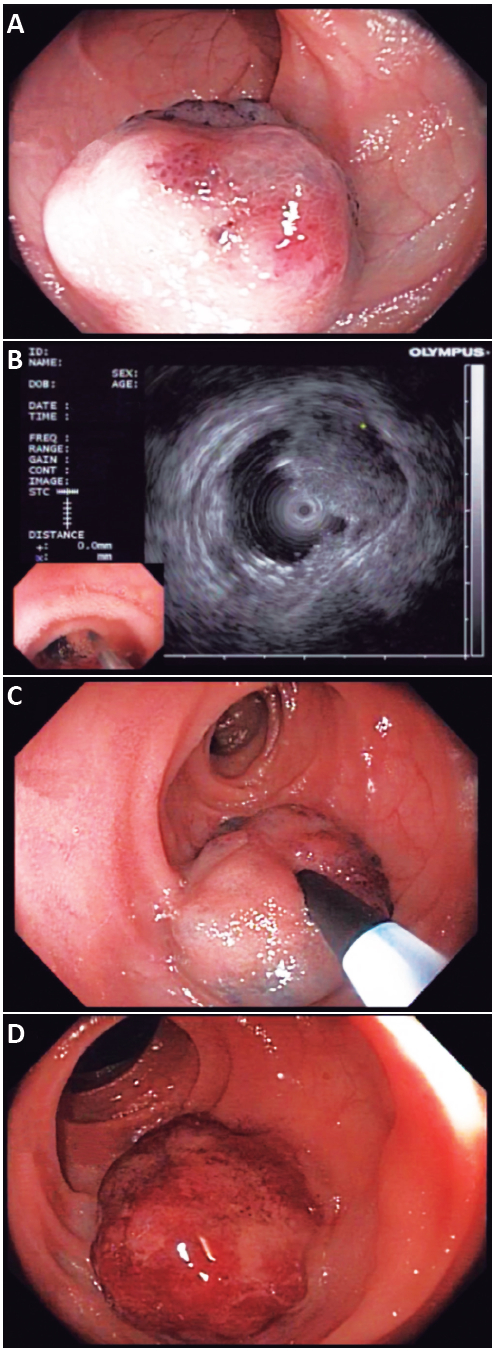

Se evaluó dicha lesión con ultrasonografía endoscópica con minisonda radial de 12 Hertz, y se observó lesión hipoecoica localizada en la capa submucosa, que podría corresponder a hemangioma. Se decidió realizar tratamiento endoscópico con escleroterapia con polidocanol al 1%. Se posicionó la lesión en hora 6, y se inyectaron con aguja de 21 gauges ocho mililitros de solución de polidocanol al 1%, evidenciándose cambio de coloración y aumento del tamaño de la lesión (Figura 1). El paciente no presentó complicaciones posteriores al tratamiento (Vídeo 2), y evolucionó favorablemente, con mejoría de los parámetros hematimétricos, sin necesidad de transfusiones ni requerimientos de hierro endovenoso.

A. Lesión elevada lobulada azulada, de 30 mm de diámetro. B. Ultrasonografía endoscópica con mini sonda radial de 12 Hertz, donde se evidencia lesión hipoecoica de 30 mm localizada en la capa mucosa del intestino delgado, compatible con hemangioma. C. Inyección de polidocanol al 1% con aguja de 21 gauges. D. Cambio de tamaño y de coloración posterior a la inyección.